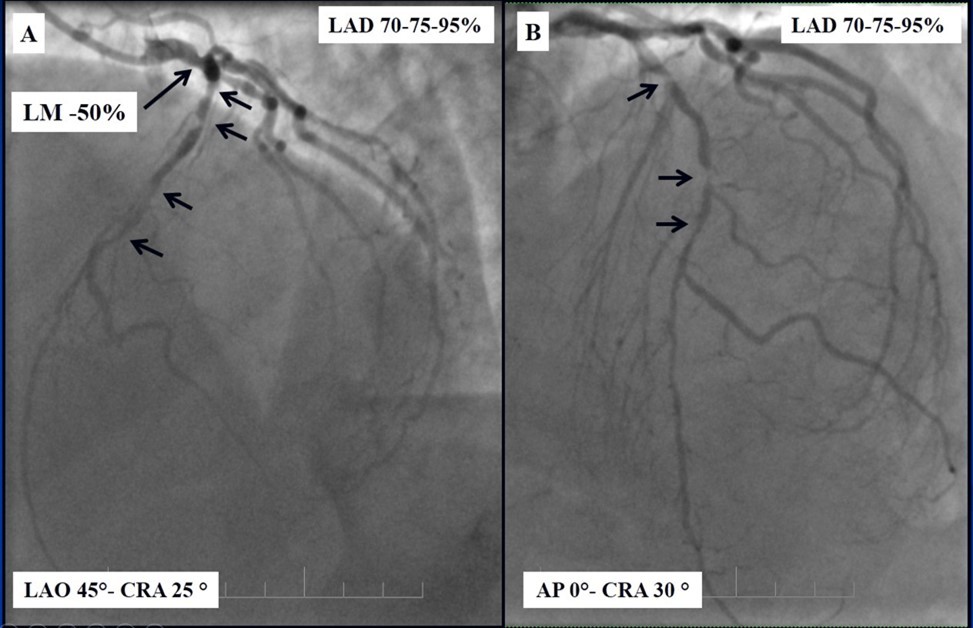

Angiography revealed rare anatomical variation LMCA quadrifurcation (Figure 1, Figure 2), 50% stenosis of the distal part of the LMCA, 40% stenosis of the ostial segment of left anterior descending (LAD) artery and diffuse prolonged 70-75-95% stenosis in mid-segment (Figure 3), 75% stenosis of the ostial segment of the circumflex (CX) artery, 75% stenosis of the ostial segment of the first marginal branch (OM1), 75-90% stenosis of the proximal segment of the intermediate artery (IMA), prolonged diffuse severe 90-95% stenosis of mid-segment of the right coronary artery (RCA) (Figure 4).

Figure 4.A - 50% stenosis of the distal segment of the LMCA; B - 70-75-95% stenosis in mid-segment of the LAD.

A - 50% stenosis of the distal segment of the LMCA; B - 70-75-95% stenosis in mid-segment of the LAD.